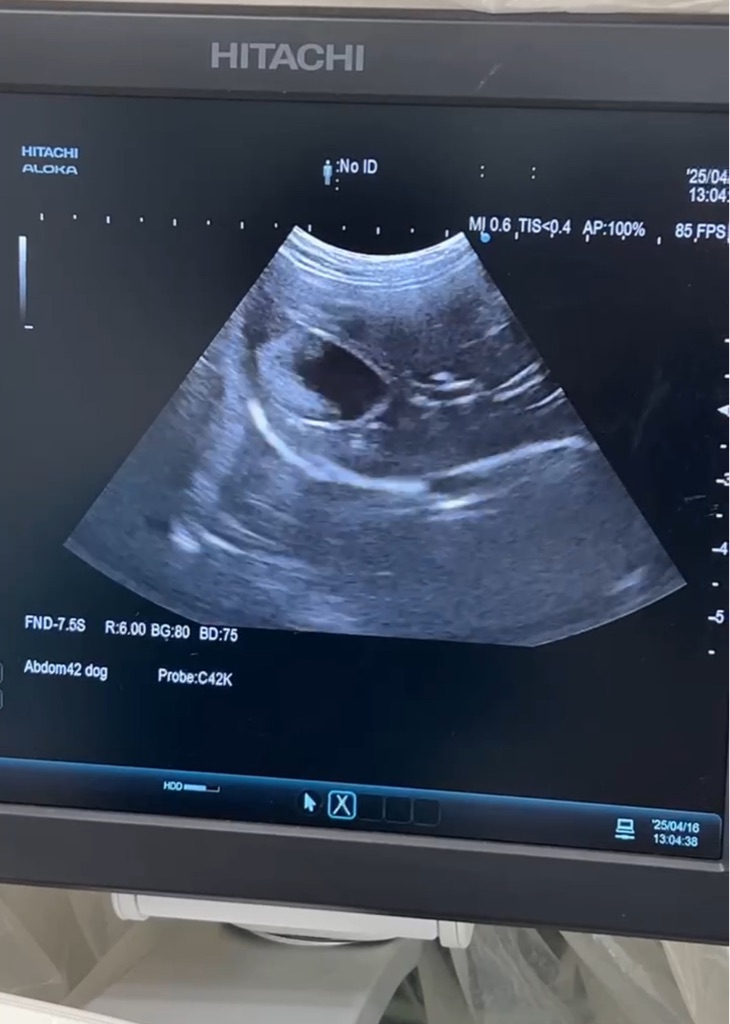

そんな中でホルモンバランスを

崩し 乳腺腫瘍や子宮蓄膿症になる子も少なく有りません。

明日、オリーブちゃんは

乳腺腫瘍6カ所の手術になります。